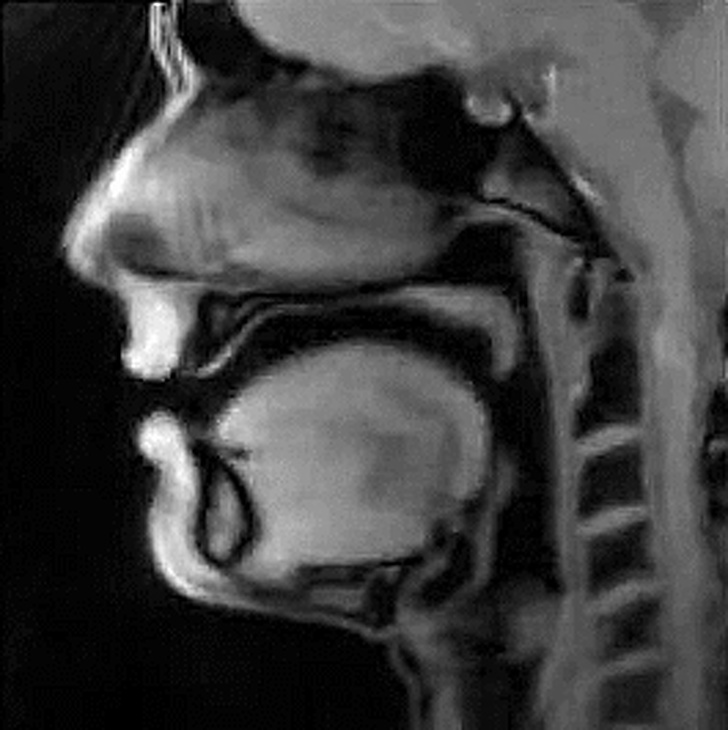

Руху мови людини під час розмови